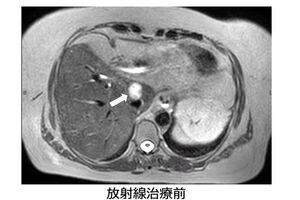

さらに、今年、最新の放射線治療が千葉大学病院に導入され、難しいとされていた膵臓がんや、肝臓がんなど、消化器に近いがんの放射線治療が可能になったという。膵臓がんといえば、5年生存率が極めて低いがんだが、最新治療によって大きく変わると期待されている。その最新治療について詳しく聞いてみた。